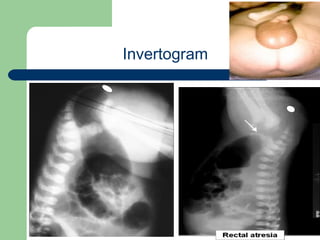

Invertogram

University of Alexandria